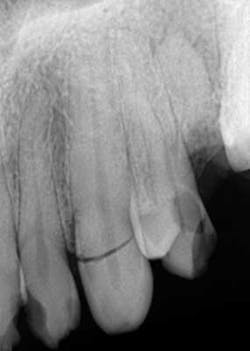

A healthy 7-year-old female presented directly from school with her father stating that she fell off the monkey bars. This was her first visit to the dentist. Initial exam revealed that tooth No. 8 was partially avulsed (Fig. 1) with only a slight attachment to the gingiva. All other teeth appeared clinically normal. Radiograph assessment revealed a large open apex on No. 8. The patient was given a local. The clot was removed and the area irrigated with a saline rinse. Next, the tooth was gently repositioned in the socket with slight compression of facial and lingual alveolar processes. A nonresilient wire splint was placed from NOs. 7 through 9. The patient was given an Rx of antibiotics for potential infection. A one-week assessment revealed a significant decrease of swelling with No. 8 appearing fairly stable. After eight weeks, tooth No. 8 had a slight delay to cold testing with all other teeth testing normal. The splint was removed. It was discussed with the father that the delayed response could be attributed to the healing of pulp or potential pathology. A two-month follow-up was recommended.